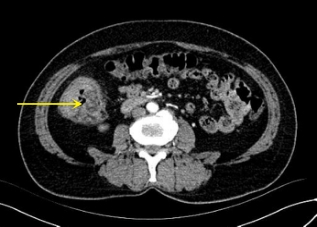

图1 术前腹部CT平扫+增强显示:回盲部巨大分叶状肿块,占据2/3肠腔Fig.1